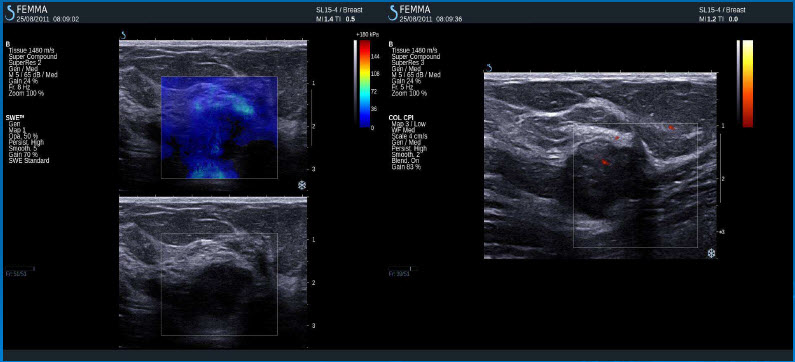

Pozitivní výsledky elastografie / histologicky potvrzená benignita

Intraduktální papilom

Fibroza